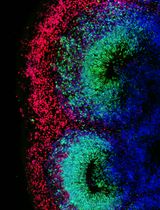

Improved Immunohistochemistry of Mouse Eye Sections Using Davidson's Fixative and Melanin Bleaching

AL Anne Nathalie Longakit

CH Chloe Hess

CZ Christina Zhang

CV Catherine D. Van Raamsdonk

1625 Views

Nov 20, 2025

Immunohistochemistry (IHC) and immunofluorescence (IF) are fundamental molecular biology techniques to assess protein expression. However, the melanin present normally in the eye in the uveal tract (choroid, iris, and ciliary body) and the retinal pigment epithelium (RPE) poses a significant challenge for IHC and IF. This is because melanin interferes with both chromogenic and fluorescent detection methods. Additionally, formalin fixation, which is commonly used for IHC, can result in shrinkage and loss of cellular detail in the eye. This protocol provides an optimized approach using Davidson’s fixative with a hydrogen peroxide bleaching step to eliminate melanin interference in the mouse eye, improving the quality and interpretability of IHC analyses of the uveal tract and RPE. It is particularly useful for the analysis of uveal melanoma.